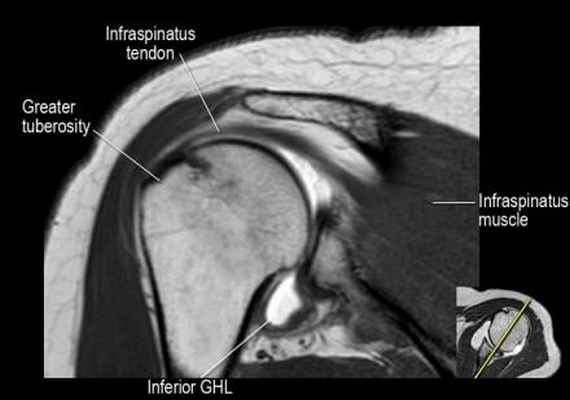

Изображение задних отделов плечевого сустава.

Отображены надостная, подостная и малая круглая мышцы и их сухожилия. Все они прикрепляются к большому бугорку плечевой кости. Сухожилия и мышцы манжеты вращателей участвуют в стабилизации плечевого сустава во время движения. Без манжеты вращателей головка плечевой кости частично сместилась бы из суставной впадины, уменьшив силу отведения дельтовидной мышцы (мышцы вращательной манжеты координирует усилия дельтовидной мышцы). Повреждение манжеты вращателей может привести к смещению головки плечевой кости кверху, в результате вызвая высокое стояние головки плечевой кости.